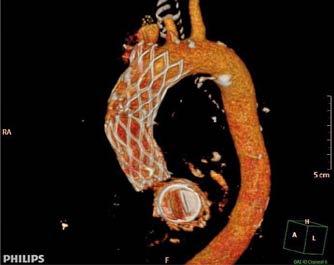

Se realizó una tomografía computarizada (TC) con contraste de forma emergente, que mostró una disección aórtica iatrogénica tipo A focal de origen en la zona 0 del cayado con extensión al tronco braquiocefálico derecho (1) sin afectar al resto de troncos supra-aórticos, cayado o aorta descendente (Figuras 1 y 2); además del hematoma

y disección de la arteria radial derecha, respectivamente. Finalmente pudo ser dada de alta tras 22 días de ingreso (Figura 3), bajo anticoagulación con acenocumarol.

Figuras 1 y 2: Prótesis aórtica migrada y disección aórtica focal tipo A, de origen en la curvatura menor del arco aórtico (zona 0) hasta la bifurcación de la arteria braquiocefálica derecha; sin afectación de del resto de troncos supra-aórticos, del resto del cayado aórtico o de la aorta descendente.